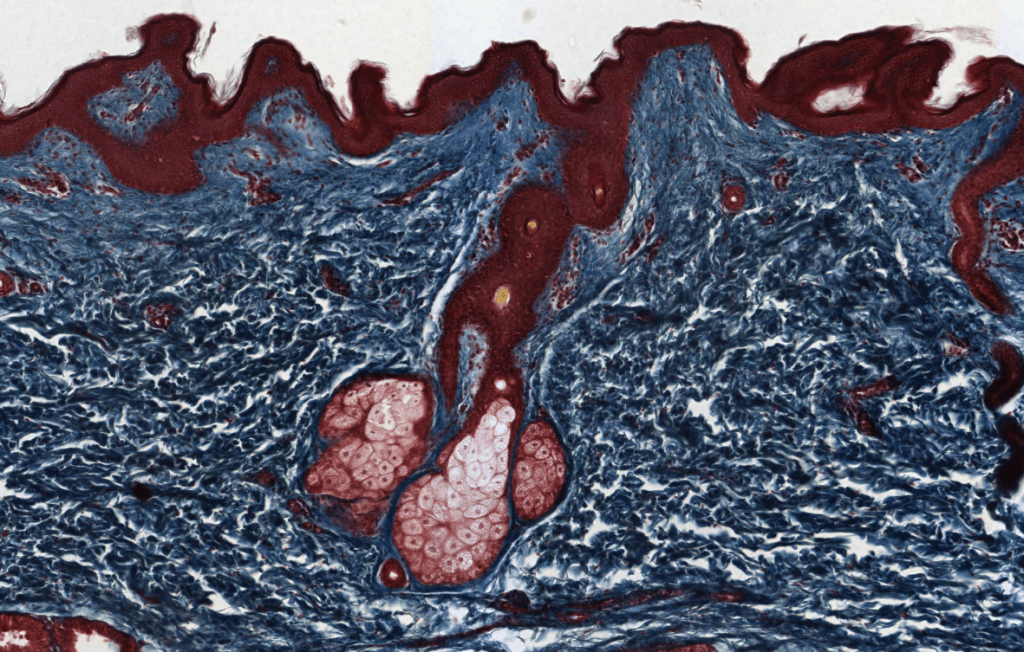

SEBÁCEAS

Su mecanismo de secreción es holocrino.

Asociadas a folículos pilosos.

Su secreción principal es sebo y este desaperec durante la técnica histológica, por eso se ve «pálido» con HyE.

Se ubican en casi toda la piel excepto piel gruesa.